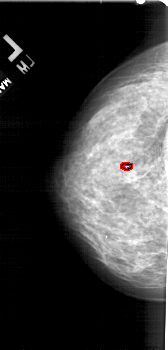

FILE: A_1755_1.LEFT_MLO.OVERLAY

TOTAL_ABNORMALITIES 1

ABNORMALITY 1

LESION_TYPE CALCIFICATION TYPE PLEOMORPHIC DISTRIBUTION CLUSTERED

ASSESSMENT 4

SUBTLETY 1

PATHOLOGY BENIGN

TOTAL_OUTLINES 1

LEFT_MLO LINES 5491 PIXELS_PER_LINE 2671 BITS_PER_PIXEL 12 RESOLUTION 43.5 OVERLAY